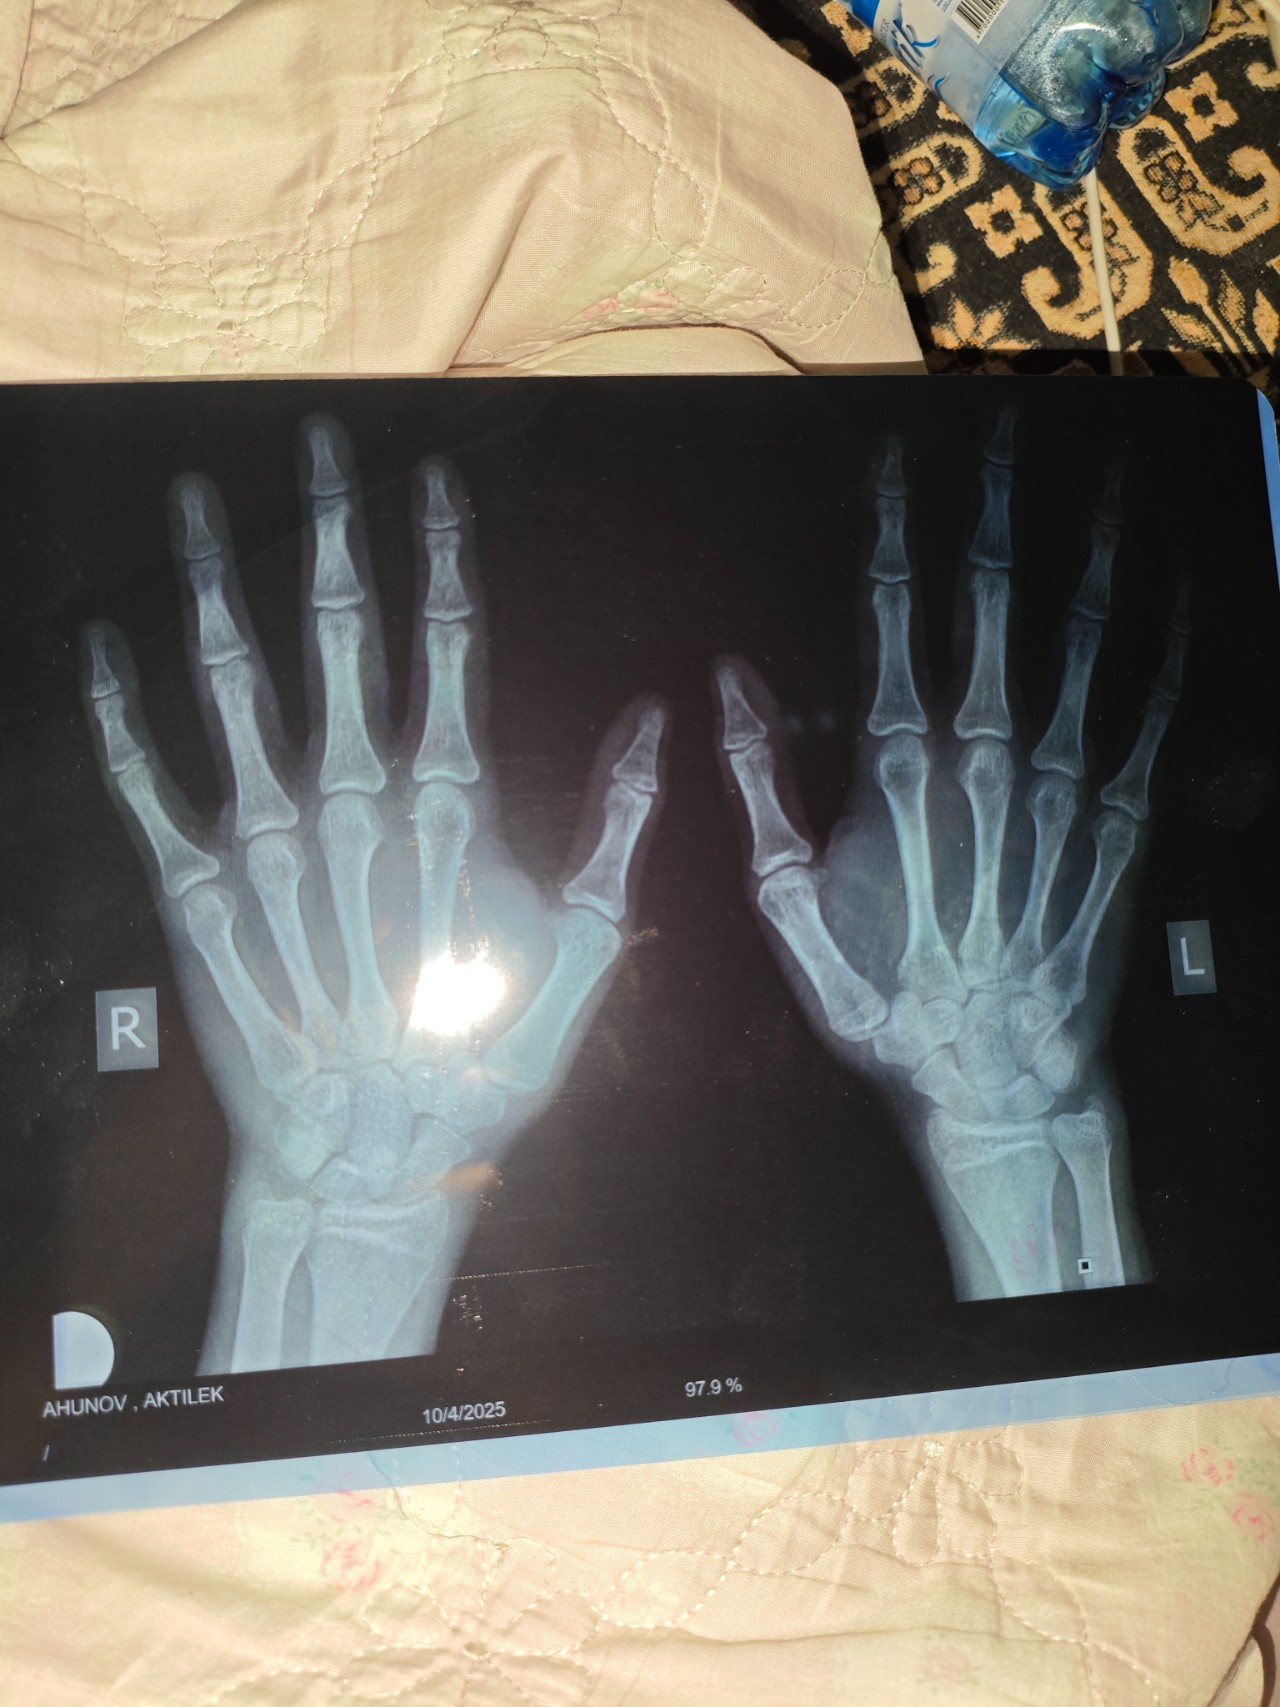

Возраст: 16 лет и 8 месяцев.

Здравствуйте, с детства был догоняющим по росту по сравнению с сверстниками. Сейчас мой рост когда сам измерял (правильно) 163-166. У эндокринолога был, она сказала, что у меня 160 рост и вес 46. И суть всего этого в том, что я бы хотел узнать, можете ли по фотографии, которые я прикреплю ниже определить мой костной возраст и закрыты ли зоны роста? Мой отец начал активно расти после 10 класса. Он ростом 181 - мама 165-169.